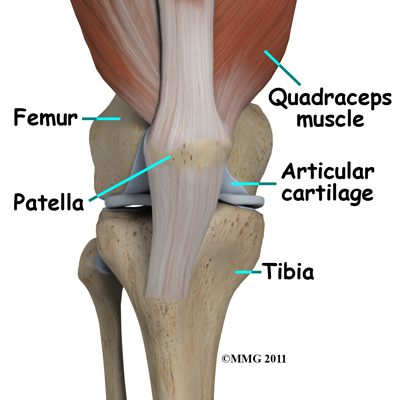

The knee joint is formed where the femur (lower end of the thighbone) connects with the tibia (upper end of the main lower leg bone). On the front of the joint is the patella (kneecap). The patella is what is called a sesamoid bone that is a part of the extensor mechanism of the knee joint. The extensor mechanism connects the large muscles of the thigh to the tibia such that contracting the thigh muscles pulls on the tibia and allows us to straighten the knee. The parts of the extensor mechanism include the thigh muscles, the quadriceps tendon, the patella and the patellar tendon.

The knee joint is formed where the femur (lower end of the thighbone) connects with the tibia (upper end of the main lower leg bone). On the front of the joint is the patella (kneecap). The patella is what is called a sesamoid bone that is a part of the extensor mechanism of the knee joint. The extensor mechanism connects the large muscles of the thigh to the tibia such that contracting the thigh muscles pulls on the tibia and allows us to straighten the knee. The parts of the extensor mechanism include the thigh muscles, the quadriceps tendon, the patella and the patellar tendon.